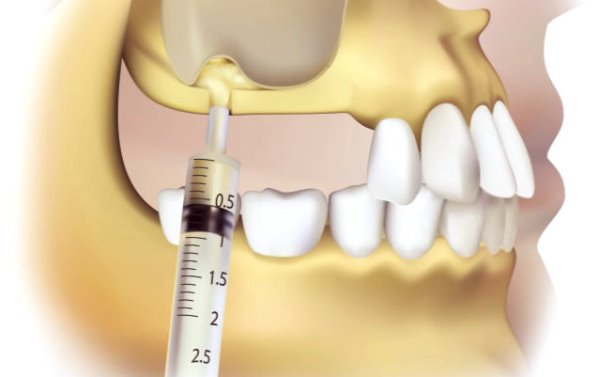

Процедура установки имплантата является одним из показателей высокотехнологичности современной имплантологии и ее комфортности для пациента. Прежде всего, операция проводится обязательно с применением сильных обезболивающих средств или полной анестезии.

Анестезия в период вмешательства в ходе имплантации зубов схожа с обезболиванием в процессе их удаления. Единственным отличием является последовательная заморозка необходимых фрагментов челюсти.

Современные анестетики созданы для того, чтобы индивидуально подходить к особенностям конкретного человеческого организма, выбирая из множества способов обезболивания для достижения 100% результата.

В случае, когда присутствуют противопоказания к средствам местной анестезии или наркозу, то здесь часто производится отключение сознания у пациента.

Следует обратить внимание, что в большинстве случаев имплантация зубов осуществляется под анестезией местного действия, когда пациент всё видит и осознаёт происходящее, так или иначе, контролируя процесс.

Применение наркоза становится альтернативным способом анестезии, если местная анестезия не оказывает нужного эффекта или противопоказана к введению конкретному пациенту.

Чтобы уменьшить болевые явления перед инъекцией, пациенту обрабатывают область укола анестетиком.

Существует несколько типов анестезии:

• Введение местных анестезирующих препаратов.

• Проведение седации. Седация – сноподобное состояние, при котором пациент практически не чувствует боли, но может реагировать на действия и слова врача.

• Введение наркоза.